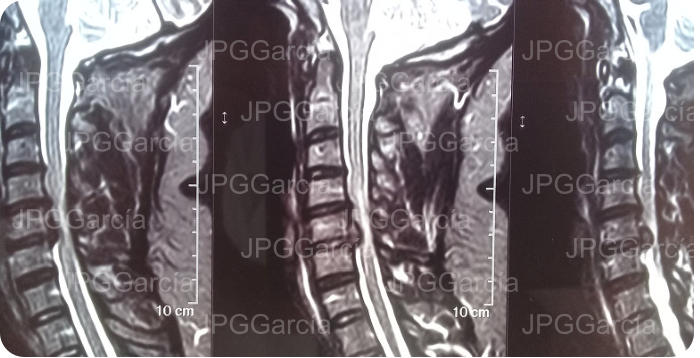

EXTRUSIÓN DE DISCO CERVICAL C4-C5

HERNIACIONES CERVICALES C4 A C6